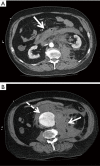

Screening abdominal ultrasound in a 52-year-old female with a family history of AAA. Line A (4.3 cm) is measured in the anteroposterior (AP) dimension and line B (5.5 cm) is measured in the transverse dimension. The standard definition for an infrarenal AAA is an aortic diameter ≥3.0 cm. AAA, abdominal aortic aneurysms.